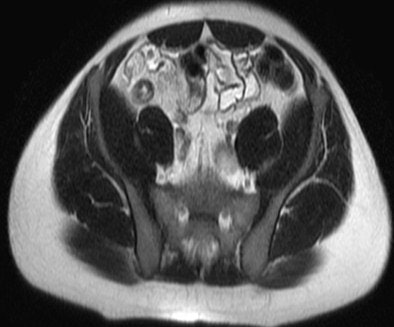

MRI results were then compared to colonoscopy and pathology reports to determine the presence or absence of disease in evaluable bowel segments. Individual imaging parameters (including wall thickening, enhancement, T2 signal, mesenteric vascular prominence, and adenopathy) were also separately analyzed to determine their independent predictive value, the authors wrote.

The study team acquired steady-state free-precession (SSFP) images of the abdomen and pelvis (TR= 4 ms, TE = 2 ms, slice thickness 8 mm for coronal images and 8-mm for axial images). Axial and coronal fat-suppressed half-fourier single-shot fast-spin echo (SSFSE) and axial spoiled-gradient images were also obtained through the abdomen, followed by T1-weighted fat-suppressed spoiled-gradient echo (LAVA/VIBE) images, before the injection of 1 mmol/kg of gadopentate dimeglumine contrast (Bayer Healthcare) followed by a saline flush and postcontrast imaging.

A single experienced abdominal radiologist, blinded to the final results, interpreted all of the MRE images, rating wall thickness, abnormal enhancement, abnormal T2 signal, and mesenteric vascular prominence on a scale of 1-4. All endoscopy reports were reviewed for mention of inflammatory changes in specific bowel segments, and pathology reports were reviewed for the presence of inflammatory disease, the study team reported.